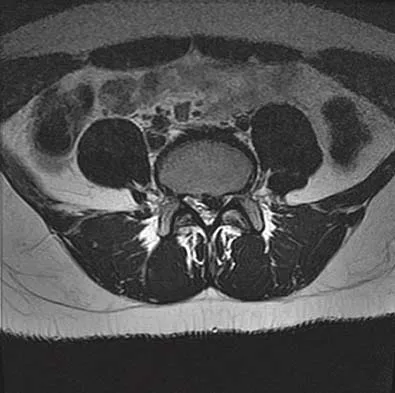

A 50-year-old man reports the onset of back pain and incapacitating pain radiating down his left leg posterolaterally and into the first dorsal web space of his foot 1 day after doing some yard work. He denies any history of trauma. Examination reveals ipsilateral extensor hallucis longus weakness. MRI scans are shown in Figures 19a through 19c. What nerve root is affected?

Detailed Explanation